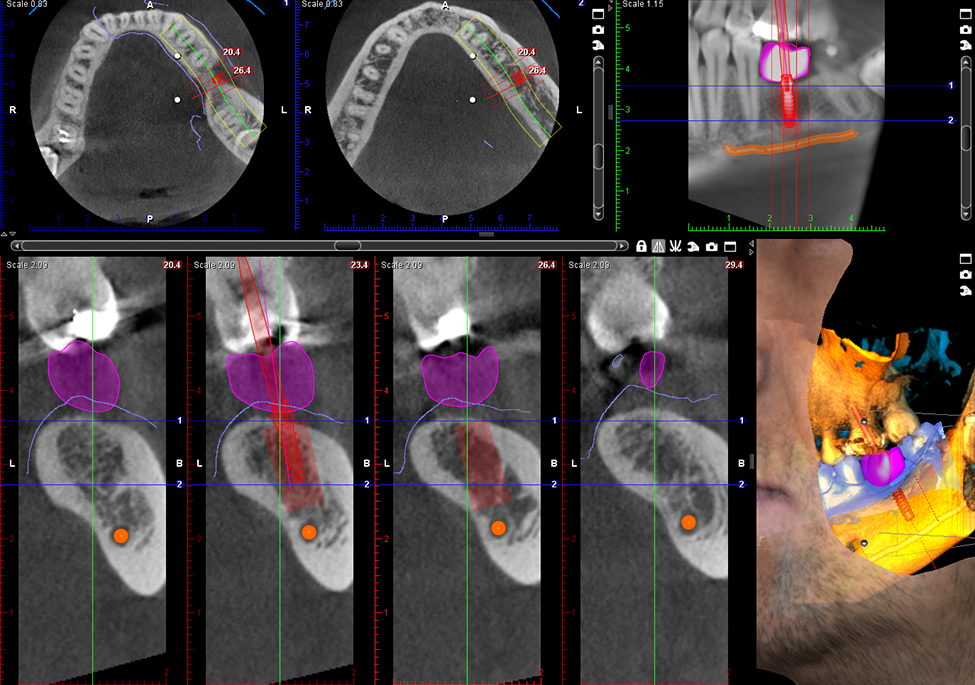

Implantologia

Implant 3D z koroną

3 x 3D = CBCT + ProFace + skan wycisku